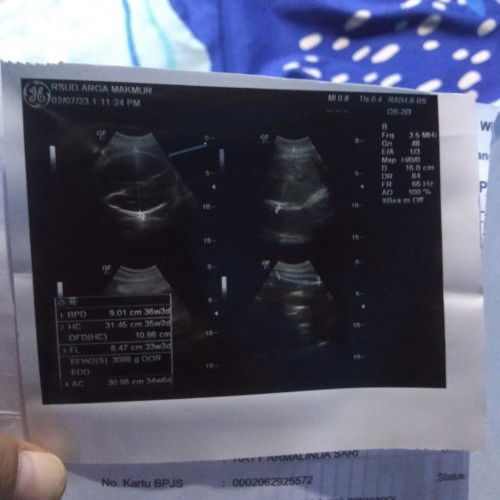

bun mau nnya,kmren sya usg di usia kandungan 34 week, nnya ke dokter bbjnya normal,cmn lupa nnya berpanya bun, di lembar usgnya ada kan bun penjelasan tentang bbjnya,tp saya ga tau yang mana bun,barang kali ada bunda2 yang tau,tlong dong bund berp bbjnya.soalnya penasaran jga bun#seriusnanya #seriusnanya